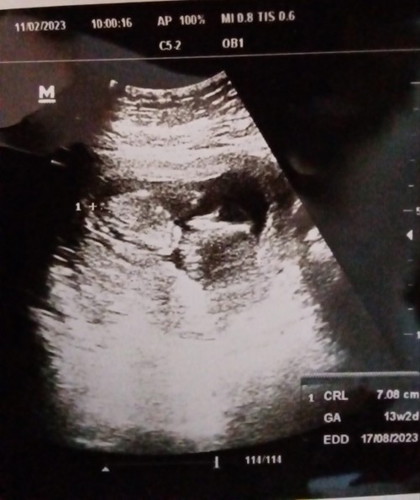

แม่ติดเชื้อซิฟิลิสค่ะ 1:2 หมอนัดไปฉีดยาแล้วค่ะ ภาพน้องตอน13w2d น้องจะออกมาแข็งแรงไหมคะ คุณหมอแค่ส่งตัวไป รพ. ตอนแรกไปฝากคลินิกค่ะ พอพบเชื้อหมอเลยส่งไป รักษาต่อที่รพ.ค่ะ